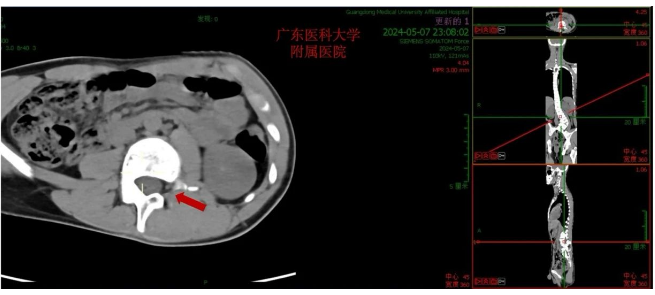

该青少年患者,腰骶段半椎体畸形,先天性脊柱侧凸,腰弯(L3-L5)Cobb角73.40°,脊柱侧凸角度大,为重度先天性脊柱侧凸,同时患者L2左侧椎弓根缺如,脊柱侧凸矫形手术难度大。根据患者具体情况,科主任魏波教授组织全科讨论评估患者病情,做了详细的术前评估,并制定了完善的手术方案及策略。

在胡资兵主任医师的指导下,由郑锦畅副主任医师及林瀚主治医生给患者行了经后路腰骶段半椎体切除、L1- L5椎弓根螺钉联合S2骶髂关节螺钉内固定、脊柱侧凸矫形、后外侧植骨融合术,手术过程顺利,术后患者康复迅速,取得满意的矫形效果,让患者挺起脊梁。

经后路腰骶段半椎体切除、L1- L5椎弓根螺钉联合S2骶髂关节螺钉内固定、脊柱侧凸矫形、后外侧植骨融合术